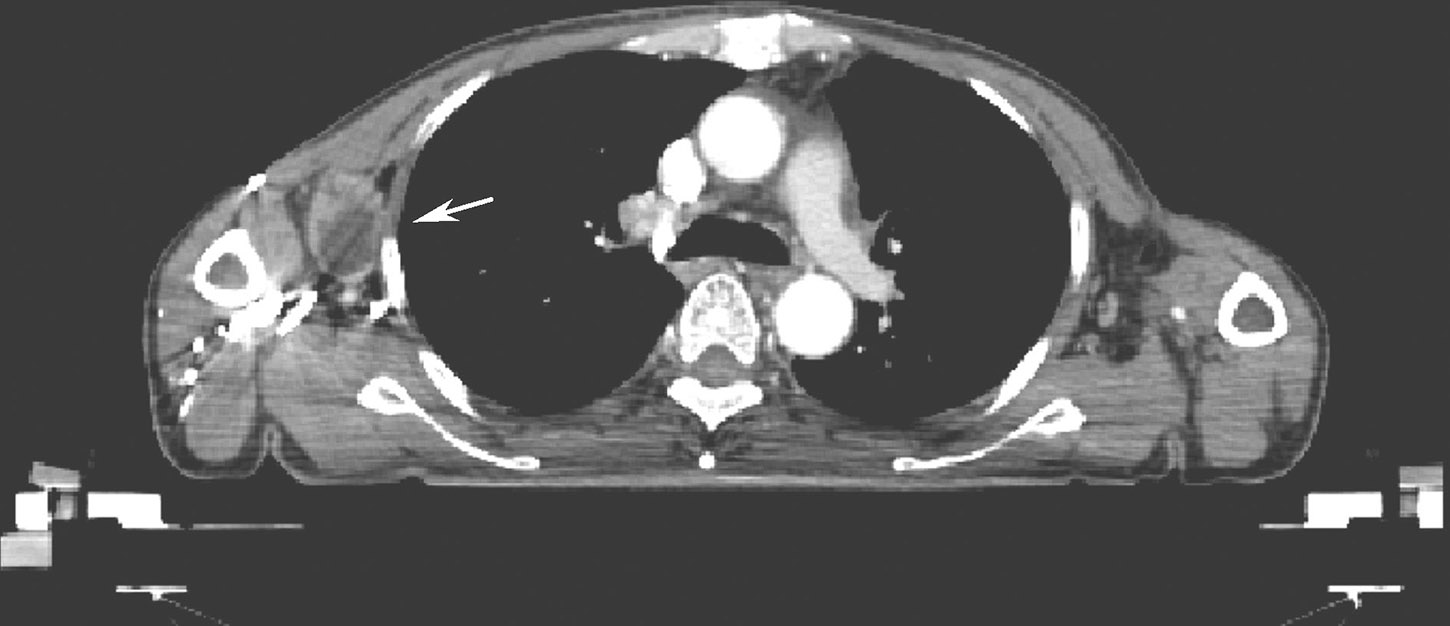

2017-06-14患者因发现腋窝淋巴结增大再次入院行CT检查,发现右侧腋窝淋巴结增大,大小约3cm×2cm(图3)。

图3 右侧腋窝3cm×2cm淋巴结,伴中心坏死